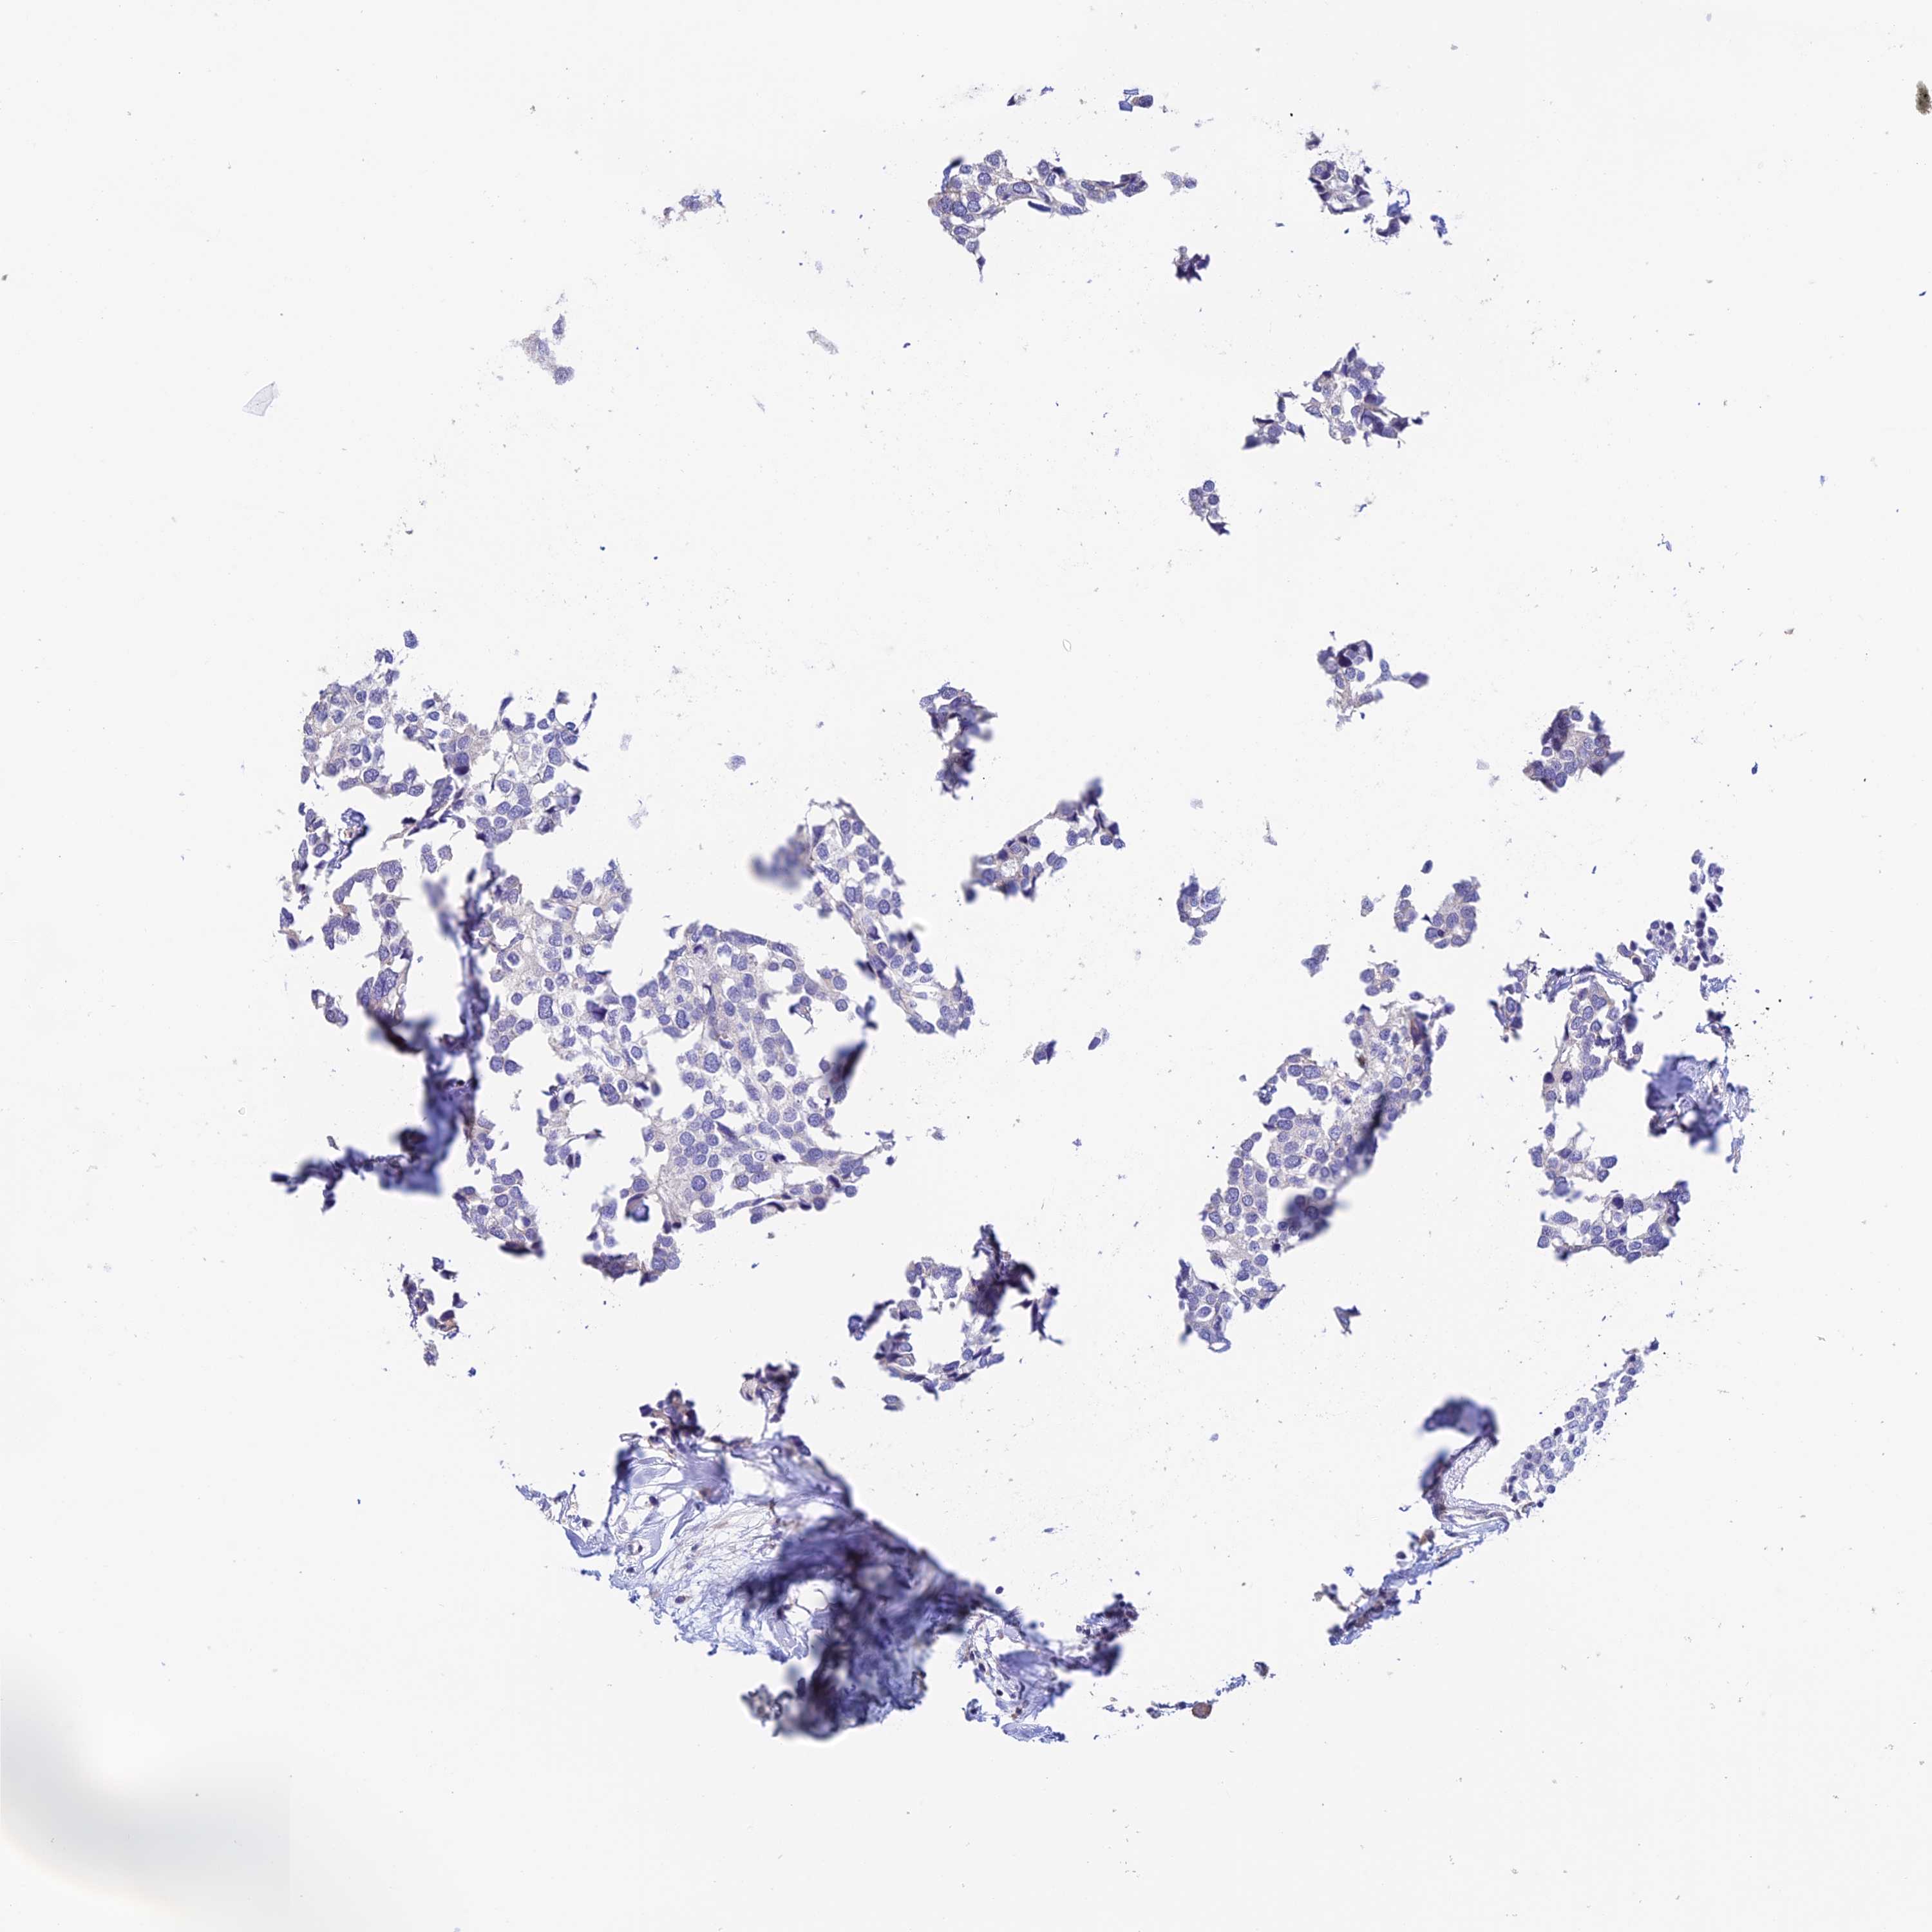

CANCER BREAST CANCER Show tissue menu

BRCA TCGA BRCA VALIDATION PROTEIN EXPRESSION